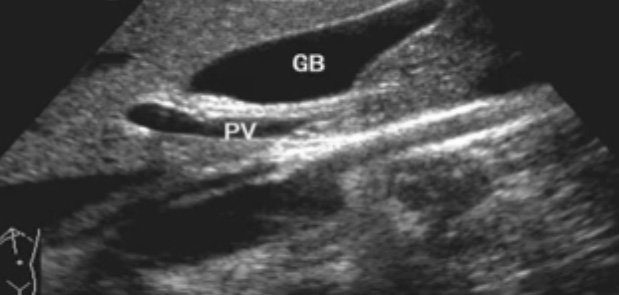

一、正常膽囊超聲圖像有的時候經(jīng)常發(fā)現(xiàn)檢查不到膽囊,其實(shí)有幾種可能性,檢查人員的技術(shù)不過關(guān)沒發(fā)現(xiàn)膽囊,就要找上級醫(yī)生會診,如果還是沒找到的話就不是技術(shù)問題。結(jié)石或腫瘤充滿膽囊,使其液腔消失,慢性膽囊炎使得膽囊萎縮或膽囊壁肥厚而囊腔消失患者已進(jìn)食,膽囊處于膽汁排空的狀態(tài),膽囊先天性過小或缺失;膽囊位置極端異常(可能很低或位于左側(cè))膽囊切除術(shù)后(注意詢問病史)。